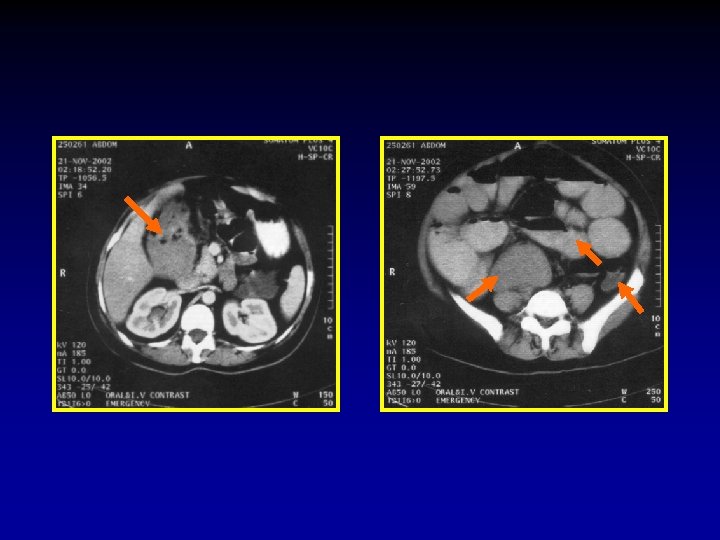

The CT signs of closed loop obstruction of the small intestine are: 1. Evidence of small bowel obstruction. 2. A U-Shaped or radial configuration of the fluid filled dilated loops. 3. At the site of obstruction, a whirl sign, beak sign, triangular loop, or two adjacent collapsed loops.

A At U-Shaped the site Evidence of configuration obstruction of. The small Whirl of two bowel theadjacent sign fluid obstruction. filled collapsed dilatedloops